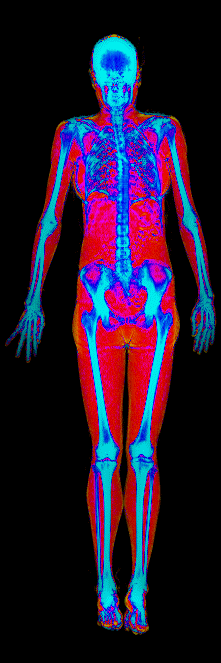

This page features real, anonymized DEXA scan images from BodyStats clients, organized by gender and body fat percentage in 5% increments. DEXA (Dual-Energy X-ray Absorptiometry) is the clinical gold standard for measuring body composition — far more accurate than scales, calipers, or visual estimates.

Each colorized scan shows the distribution of fat tissue (shown in warmer colors) and lean tissue (cooler colors) throughout the body. Compare your own DEXA scan to others in your range, or see what different body fat levels actually look like on a scan.

Female DEXA Scans by Body Fat %

15 to 20% body fat